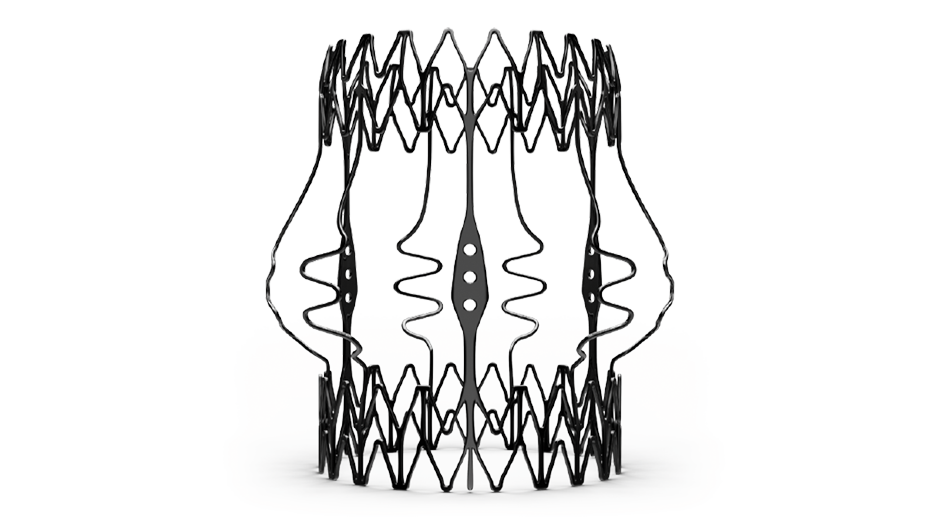

Superlastic stent

- Self-expands in place (no need to knot the sutures), ensuring optimal valve sealing.2

- Reduces the stress transferred to the leaflets.4

- CarbofilmTM coated to reduce inflammatory reaction and favor a gentle endothelialization.5,6,7

Perceval Plus boasts a distinctive design built around a superelastic stent that self-expands in place (no need to knot the sutures), ensuring optimal valve sealing.2

The Nitinol stent allows Perceval Plus to follow the physiological movement of the aortic root during the cardiac cycle, mimicking the native valve.10,11

Designed for the future: the ideal docking station for Valve-in-Valve

Perceval Plus is a valve designed for the future. Not only is it durable,9 but it also gives patients even broader treatment options for their future. Its exclusive stent design allows even circumferential expansion to accommodate future transcatheter valves, making Perceval Plus ViV friendly by design. Thanks to its unique features, all patients eligible for biological AVR may benefit from a Perceval Plus implant.**12,13

The Nitinol stent provides clear visibility under fluoroscopy and CT scan to identify landmarks which facilitate the ViV procedure.

Even circumferential expansion

The inflow ring can be evenly and circumferentially expanded up to 2.5mm above its nominal size, which allows for hemodynamic advantages and greater compatibility with TAVI models and sizes.